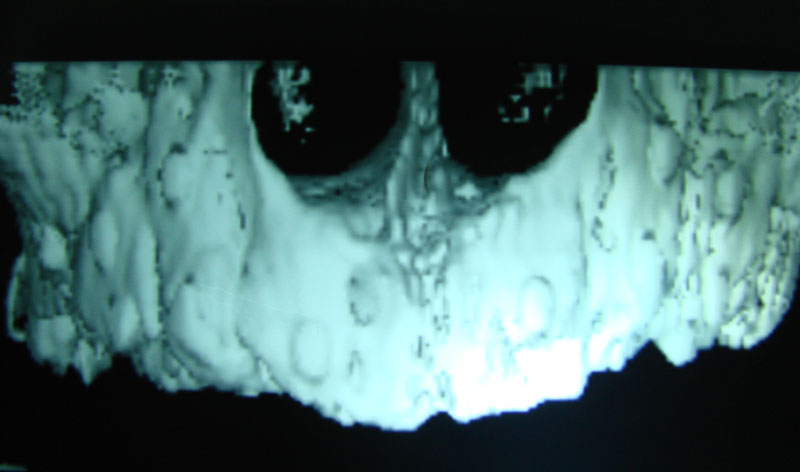

Existen muchas situaciones donde la pérdida y la atrofia ósea son tan graves que nos obligan a recurrir a la cresta iliaca del paciente, para conseguir el volumen óseo necesario para la correcta reconstrucción del maxilar. Así, la colocación de implantes será posible a los 3 meses.